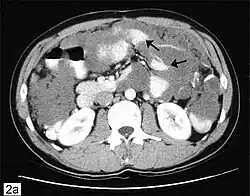

Im Ultraschallbild (Sonografie) zeigt sich eine echofreie, intraperitoneale, schleimige Masse in der gesamten Bauchhöhle und zwischen den Darmschlingen, in die charakteristische, zarte, streifige Reflexe eingelagert sind. Die Gallerte ist beweglich und verformbar, reagiert aber träger als ein klassischer Aszites. Aufgrund der Zähflüssigkeit zeigen sich groteske, tumorartige Formen.[4] Eine Computertomographie zeigt die Ausdehnung des Pseudomyxoms. In Abhängigkeit von der Ausdehnung sind eventuell zusätzlich endoskopische Untersuchungen von Magen oder Dickdarm, wie Darm- und Magenspiegelung, urologische Untersuchungen oder auch Untersuchungen von Herz und Lunge sowie Blutentnahmen nötig.[2] Als entscheidendes diagnostisches Merkmal gilt die extrazelluläre Schleimproduktion in der Bauchhöhle.[1]